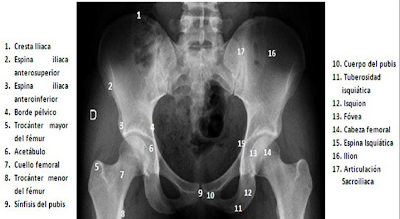

| Anatomía radiológica de la Pelvis |